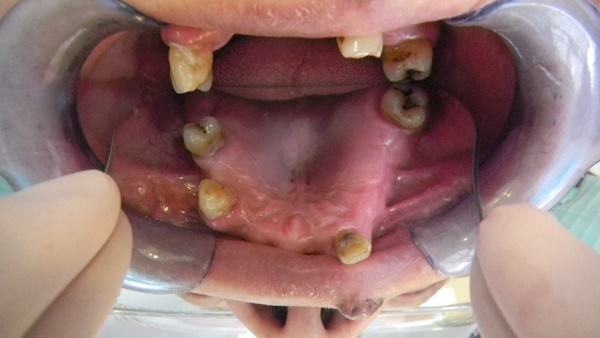

發現他咬排骨的時候很是吃力,

說他老了牙齒不中用,

甚至已經有好多顆缺牙,

過程中植牙專科朱醫師先看過阿公口腔狀況,

並建議我們幾項合適的全口重建治療方式,